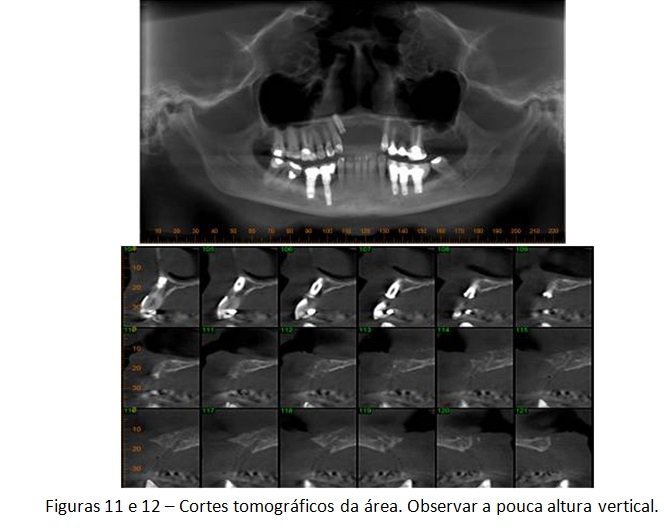

A paciente em questão foi diagnosticada com peri-implantite e recebeu tratamento cirúrgico para eliminação dos sinais e sintomas dessas alterações, mas a doença recorreu e ela acabou perdendo os implantes. A solução escolhida por nós foi o levantamento da cavidade nasal para possibilitar a colocação de dois novos implantes, viabilizando uma futura prótese fixa de quatro elementos. Veja a descrição detalhada do caso abaixo.

O levantamento do assoalho da fossa nasal, apesar de pouco divulgado, pode ser uma interessante solução para casos como esse descrito hoje. Obviamente que poderíamos ter adotado outros tipos de técnicas para se reabilitar a área. Contudo, qualquer outra alternativa teria sido muito mais invasiva, aumentando a morbidade e o tempo de tratamento. Mesmo sabendo que a prótese final será uma reabilitação “dento-gengival”, onde usaremos muita gengiva artificial, acreditamos que essa solução ainda é a melhor escolha em função de todo o histórico do caso e da paciente.